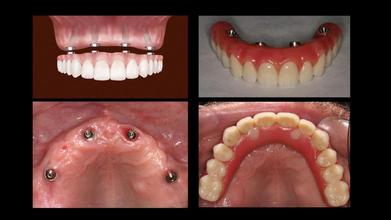

3、植體固定式假牙——All on 4全口重建/all-on-6全口重建

All on 4/all-on-6全口重建係針對骨骼嚴重萎縮、而且需要快速恢復牙齒的人而設計嘅。同傳統植牙相比,最明顯嘅優勢就係速度,若口腔條件允許,最快可以在一日之內完成全口植牙與假牙,唔需要好似傳統植牙一次等待3~6個月以上嘅治療週期。

All on 4/all-on-6全口重建只需要四顆或者六顆植牙,可以大幅縮短手術時間、節省植體費用。

無論是固定式假牙All on 4、All on 6,使用單顎4支/6支植體做為人工牙根,固定於牙床上,藉由拱橋力學設計原理,平均分散植體力量去支撐整排假牙。因此,固定式植牙最接近自然牙的假牙形式,唔單單穩定性高、咬合力佳,亦沒有活動式假牙的異物感。

配合一日全口重建療程,當日手術後,裝上臨時假牙,即可有牙恢復咬合力。